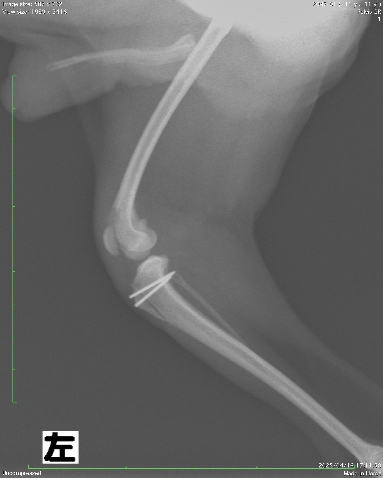

術後X線写真

膝蓋骨脱臼は正常な位置に整復されており、使用したインプラントの位置も適切であると判断致しました。

術後は3日ほど制動と術後の浮腫を軽減するために包帯にて保護します。その後は2ヶ月ほど運動制限をかけ、骨折線の癒合を待ちます。